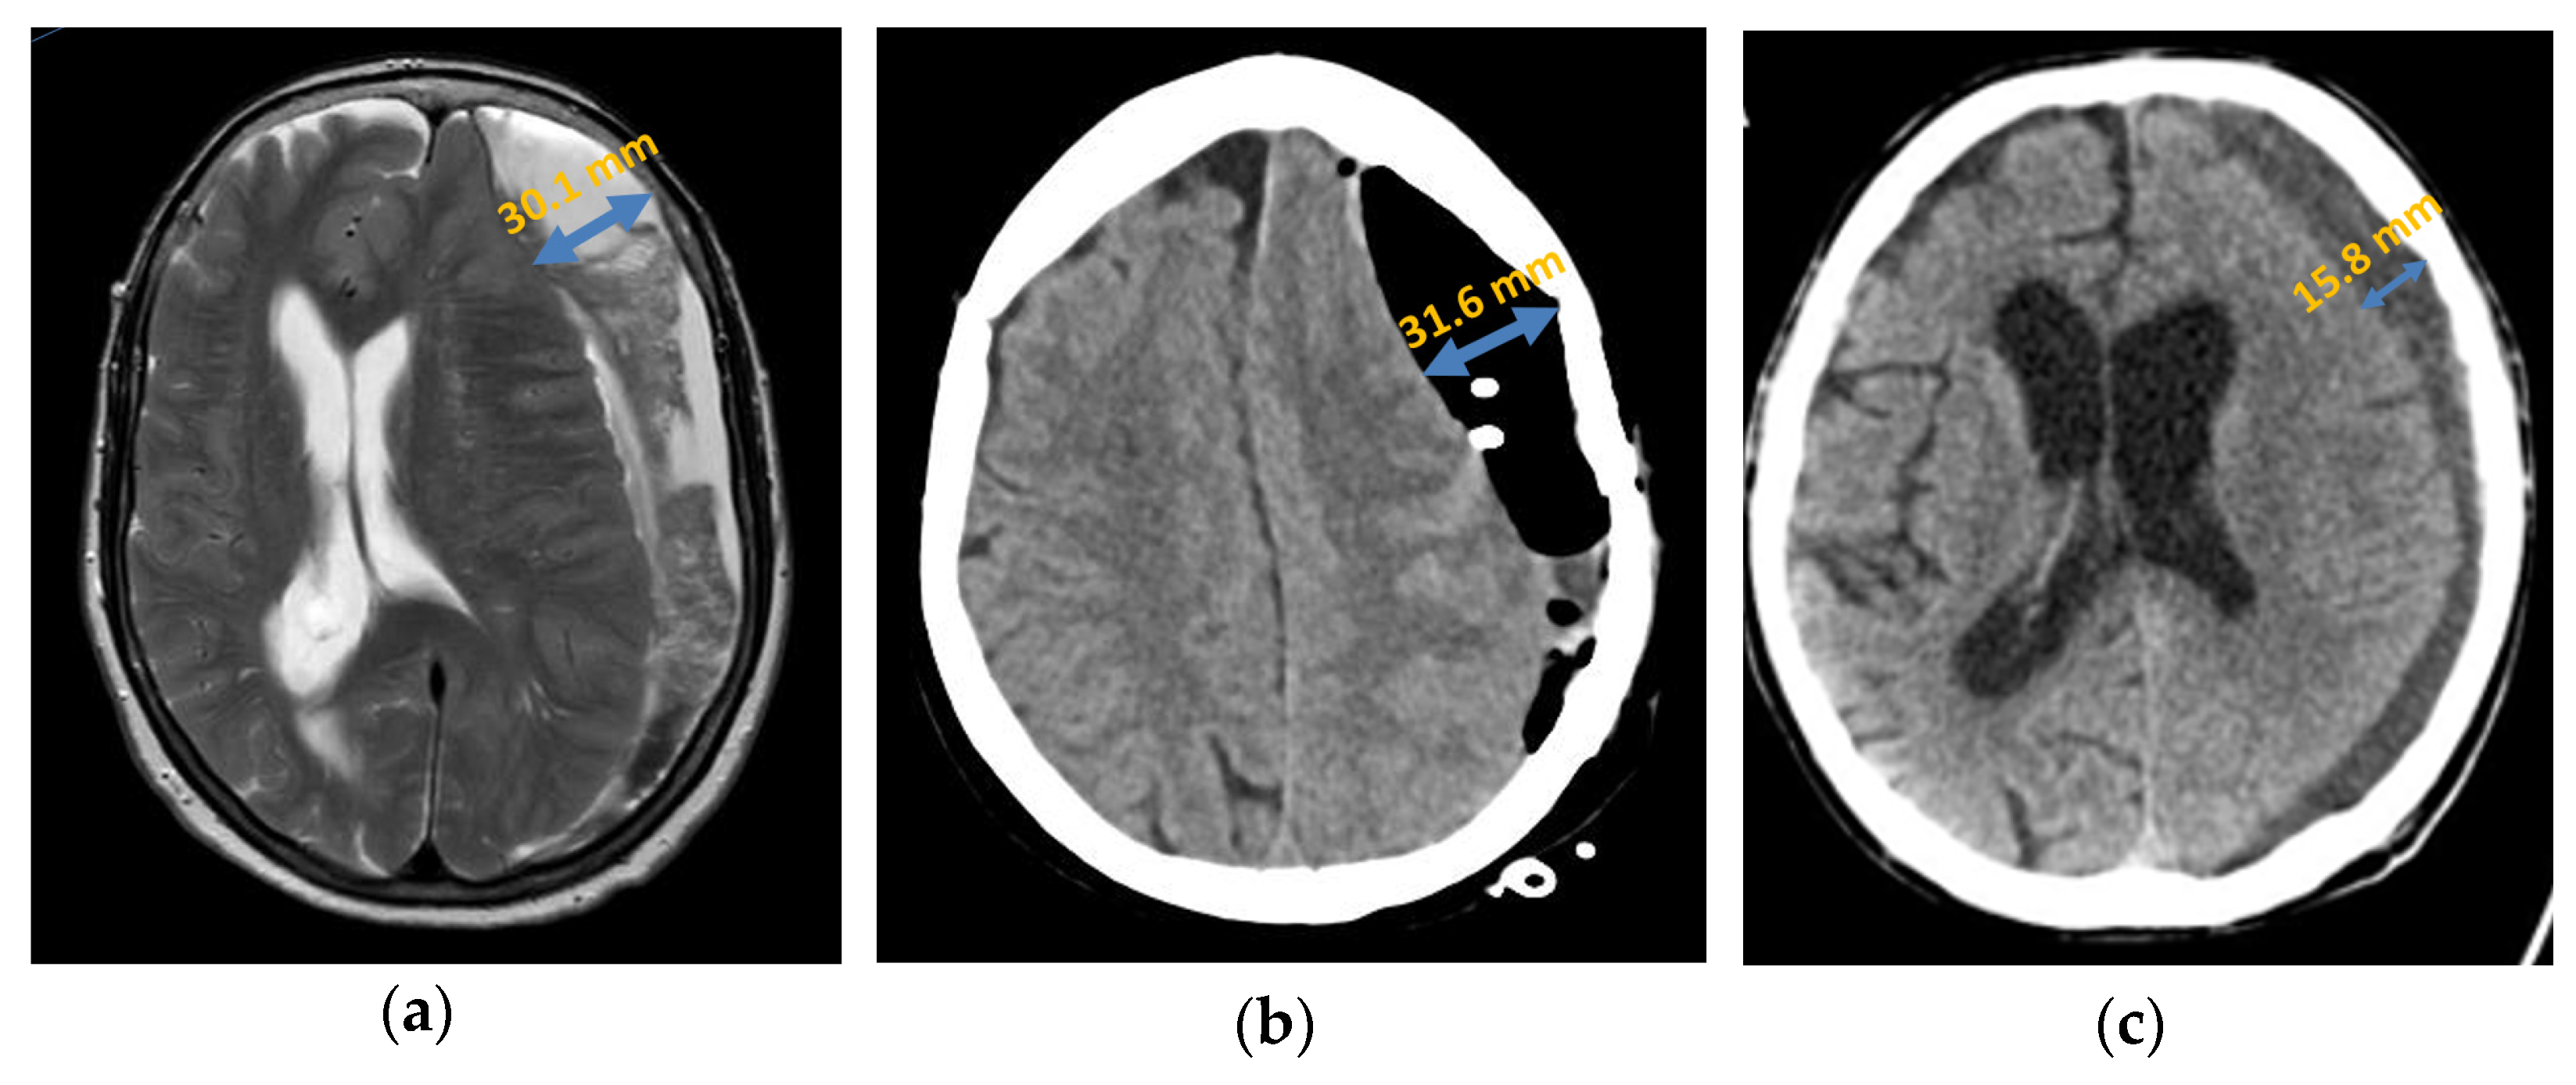

Septation

Primary septation of the chronic subdural haematoma was detected in 33.33% (n = 10) of patients with a recurrence either intraoperatively or by an imaging procedure (Figure 4). In the patient group with no recurrence, septation was detected in only 8.33% (n = 5). After analysis using Fisher’s exact test, which yielded a p-value of 0.005, septation was statistically significantly associated with an increased probability of recurrence in a chronic subdural haematoma.

Figure 4.

Axial presentation chronic subdural haematoma: (a) preoperative septation in axial plane in MRI; (b) postoperative subdural air accumulation in CT; (c) recurrence of chronic subdural haematoma in CT.

Generally, in the patients in whom septation was detectable, the recurrence rate was 66.67% (n = 10). However, in patients without detectable septation, the risk of recurrence was significantly lower at 26.67% (n = 20).